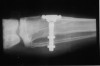

Figure 42 – Radiograph of a fractured posterior implant.

Figure 42

Figure 43 – Gingiva incised and a trephine drill used to remove the fractured implant.

Figure 43